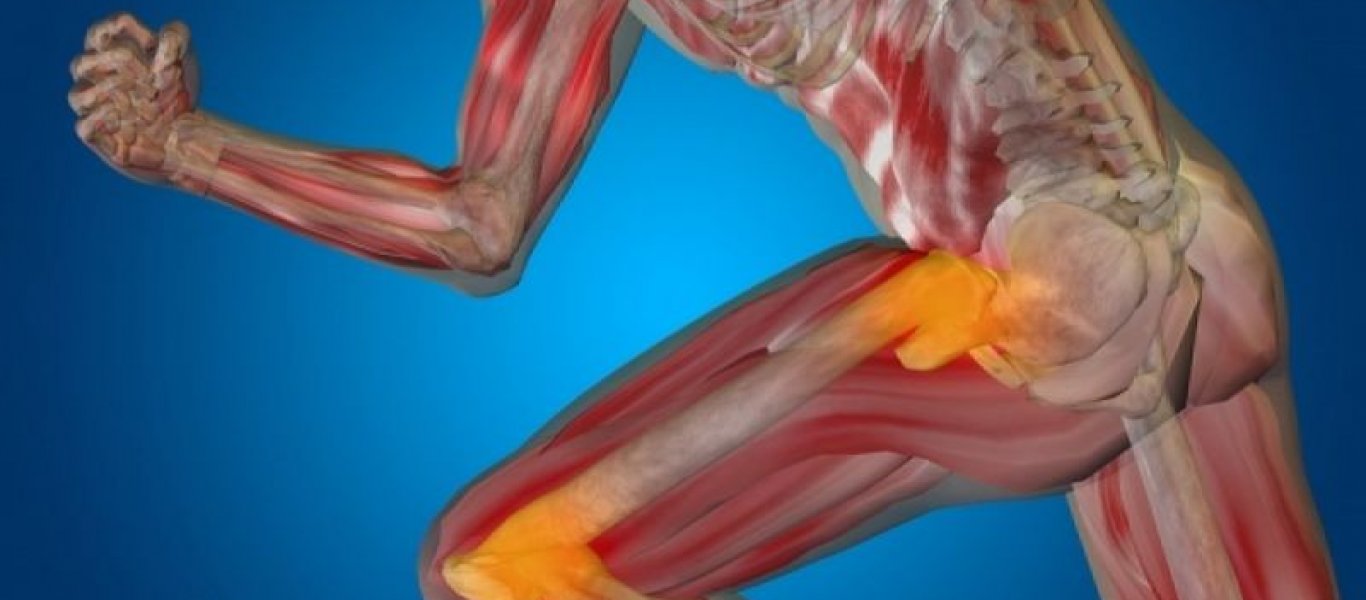

Νομίζεις ότι το γάλα είναι η Νο.1 τροφή που θα σε προστατέψει από την οστεοπόρωση; Ξανασκέψου το!

Σύμφωνα με Αμερικανούς ερευνητές υπάρχει μια φυτική τροφή που μπορεί να σού χαρίσει πολύ πιο γερά κόκαλα!

Ο λόγος για τα δαμάσκηνα, τα οποία σύμφωνα με την έρευνα επιβραδύνουν την οστεοπόρωση σε γυναίκες που βρίσκονται σε εμμηνόπαυση, αλλά και σε άντρες. Το αγαπημένο φρούτο του καλοκαιριού έχει σπουδαίες ποσότητες μετάλλων, όπως ο χαλκός, το μαγνήσιο και το σελήνιο που είναι υπεύθυνα για την ενίσχυση των οστών, καθώς προστατεύουν από την οστεοπόρωση.

Ακόμη και αν δεν είναι καλοκαίρι όμως μπορείς να απολαύσεις τις ευεργετικές του ιδιότητες, καταναλώνοντάς το ξηρό ως σνακ ή προσθέτοντάς το στα δημητριακά και τις σαλάτες σου. Τα ξερά δαμάσκηνα περιέχουν, επίσης, το ιχνοστοιχείο βόριο, που συμβάλλει στην καλή υγεία των οστών.

Μην νομίζεις ότι πια θα πρέπει να τρέφεσαι μόνο με δαμάσκηνα. Πέντε με έξι φρούτα είναι αρκετά για να δεις σπουδαία διαφορά στην υγεία των οστών σου.